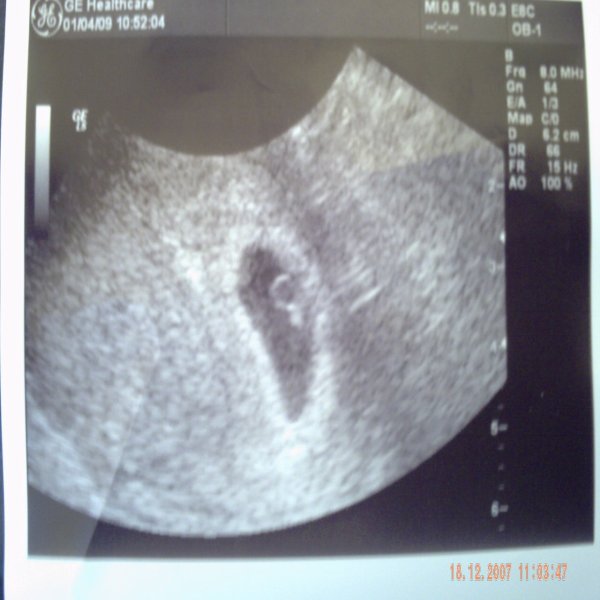

4,5 mm a kis pöttöm és él, 140-et ver a kis szivecskéje, imádom!!!!!!!!!!!!!!!!

Ime őfelsége:

Kép

kicsit közelebbről:

Apának mondtam, hogy nagyon hasonlít rá épp olyan nagy feje van mint neki! :lol: :lol: :lol: :lol: Erre visszavágott hogy a pöcse is akkora lesz! :twisted: :twisted: :twisted: